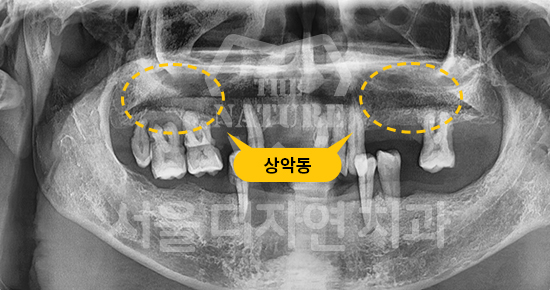

#Sinus Lift

-

BEFORE: 2021.02.01

AFTER: 2021.05.13